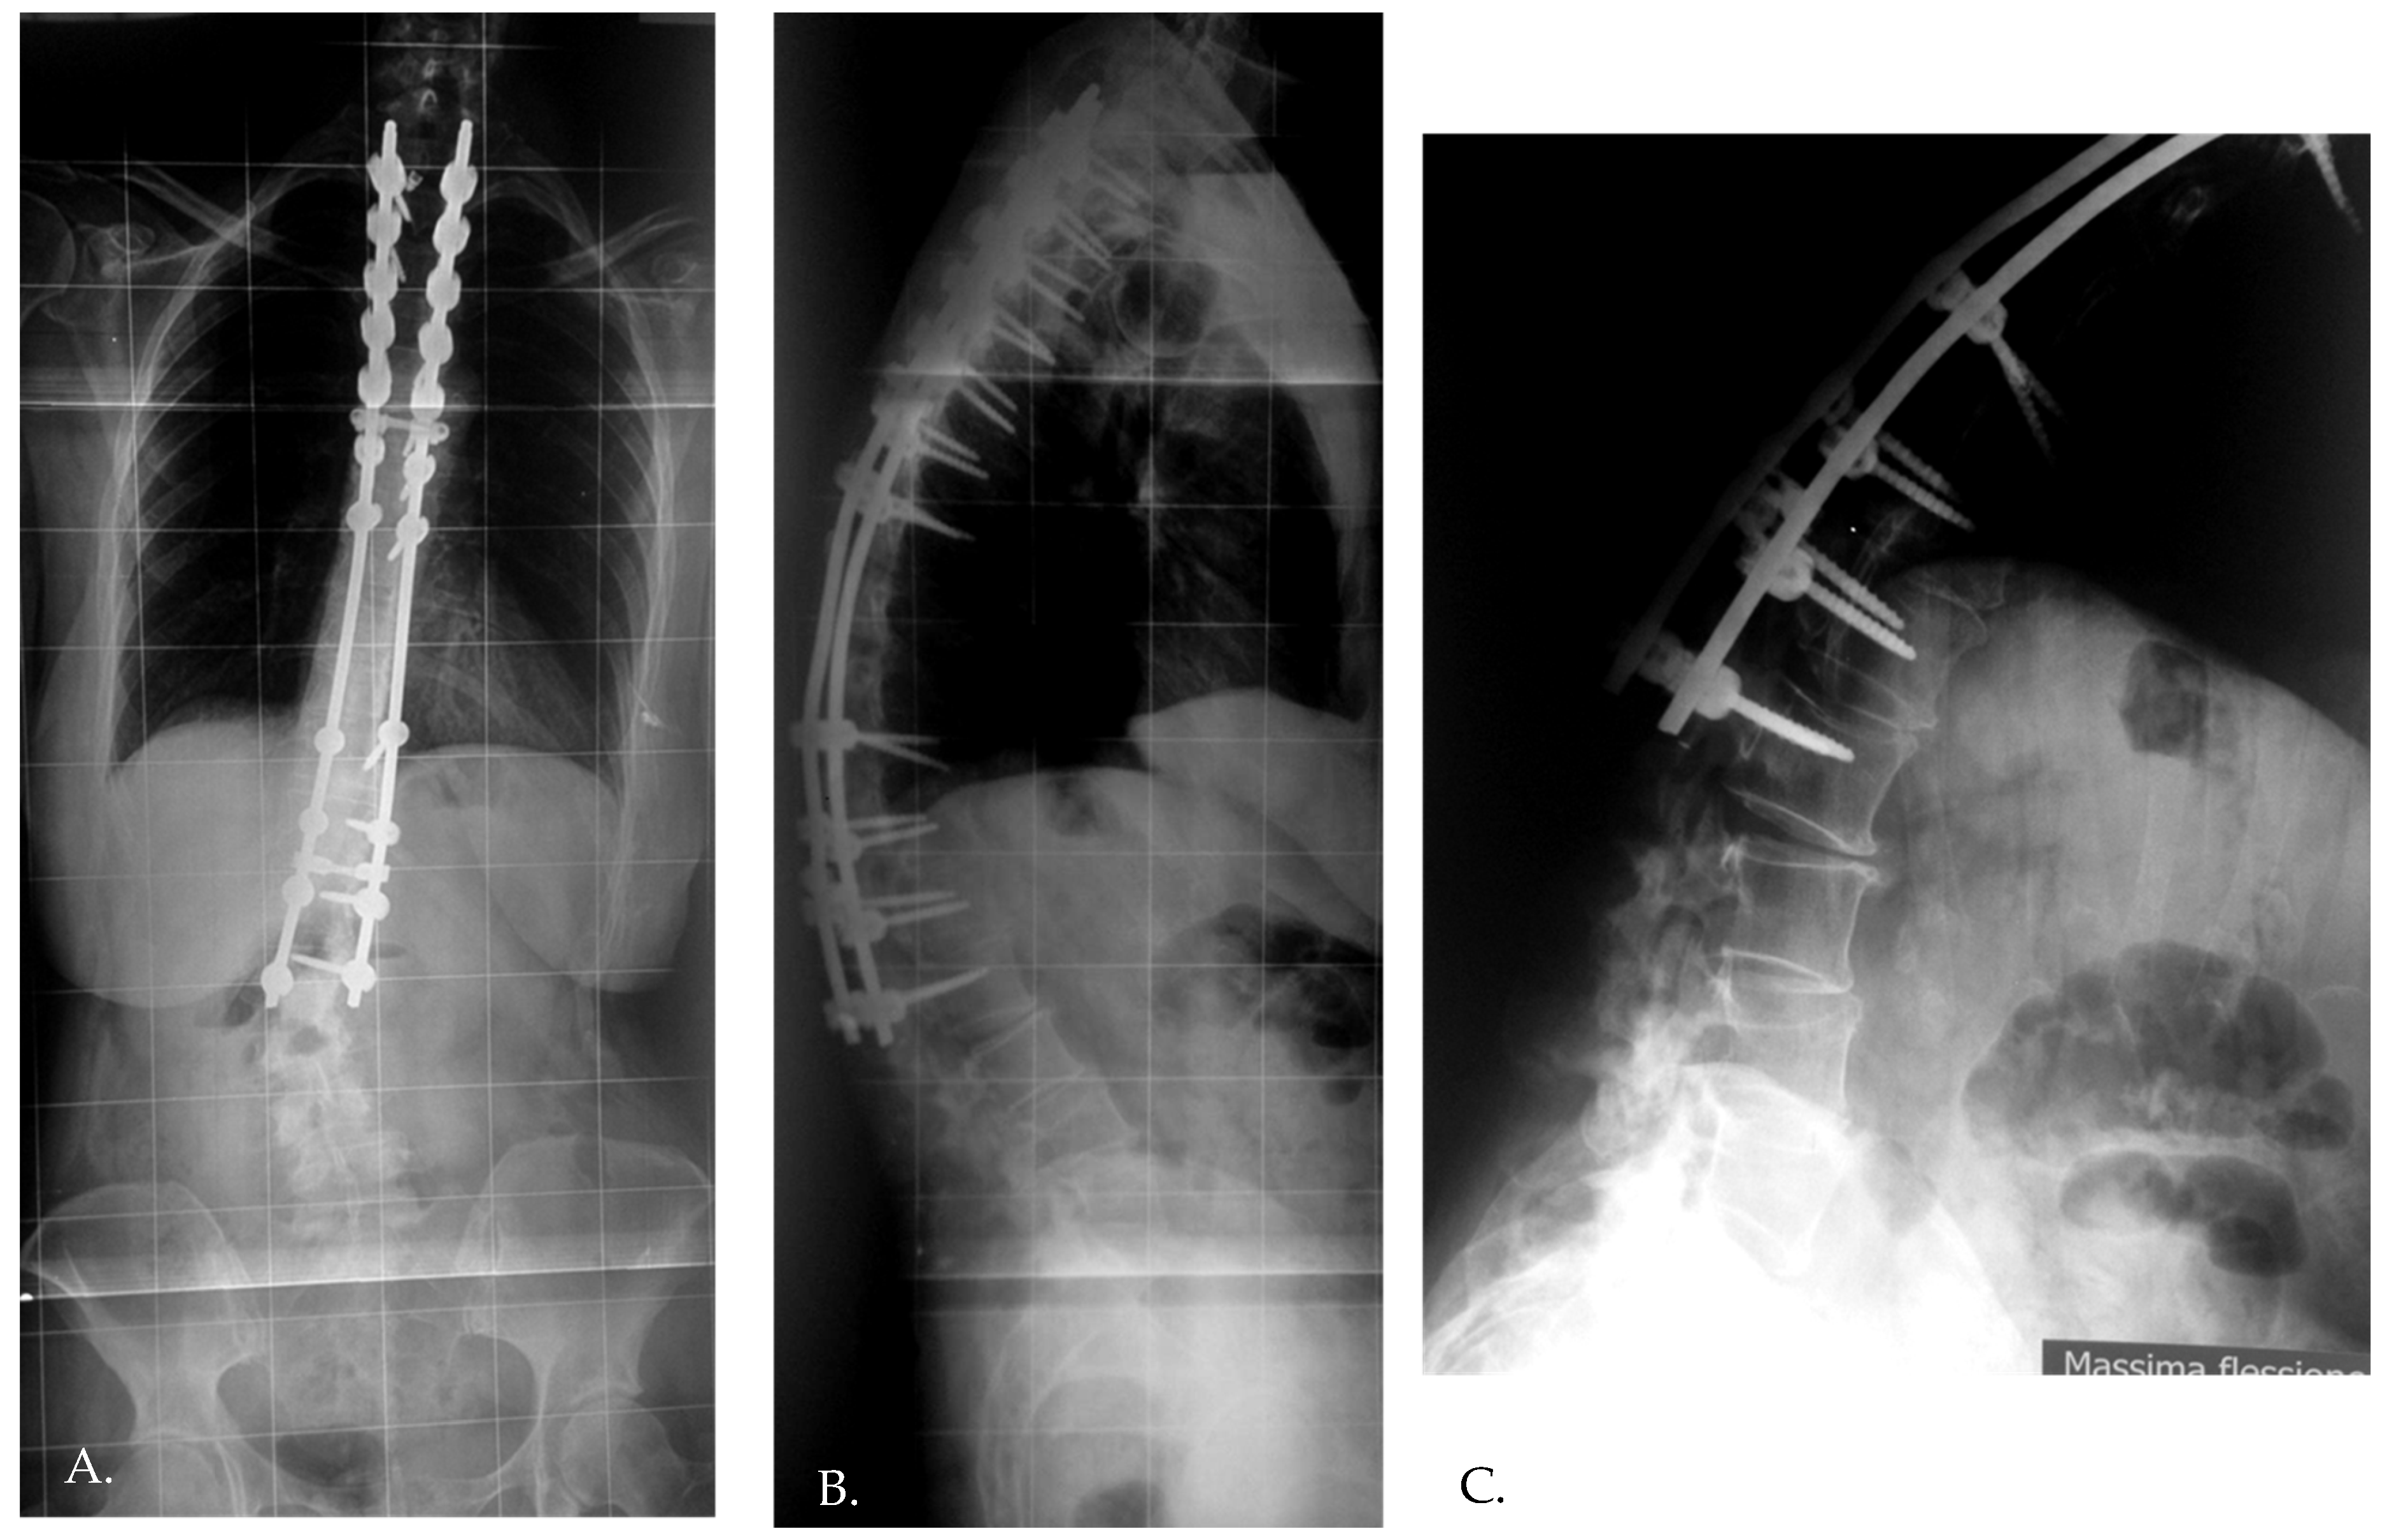

- In Group 1, the mean preoperative DJA was 4.8° (range: 2.2–7.4°), which decreased to 2.2° (range: −7.5° to 6.1°) immediately postoperatively (p = 0.005). At the final follow-up, the DJA was 0.7° (range: −8.3° to 6.1°).

- In Group 2, the mean preoperative DJA was 7.9° (range: 0.2–8.4°), which decreased to 5.6° (range: 0.2–8.5°) immediately postoperatively (p = 0.009). At the final follow-up, the DJA was 4.9° (range: 0.2–7.1°), with a non-statistically significant correction loss of 0.7°.